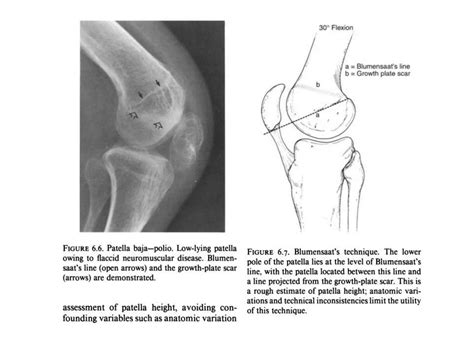

Patella dislocations | PPTX

Patella dislocations | PPTX